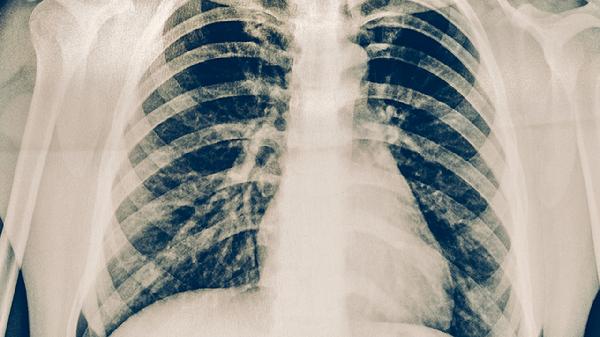

肺癌同侧转移指肿瘤细胞扩散至原发灶同侧肺门或纵隔淋巴结,甚至邻近器官。若转移灶局限且未侵犯重要血管或器官,患者心肺功能良好,手术切除原发灶及转移淋巴结可提高生存率。此时手术需确保切缘阴性,并联合系统性淋巴结清扫。术后病理检查可明确分期,指导后续辅助治疗。对于非小细胞肺癌,手术联合化疗或靶向治疗能显著延缓复发。

若转移范围广泛或侵犯心脏大血管、气管等关键结构,手术风险超过获益,则不建议直接手术。此类患者可能需先通过新辅助化疗缩小病灶,再评估手术可行性。小细胞肺癌因恶性度高、早期易转移,通常以放化疗为主,仅极少数局限期患者可考虑手术。合并严重肺气肿、心功能不全等基础疾病者,手术耐受性差,需优先选择姑息性治疗。

确诊肺癌同侧转移后,应通过PET-CT、脑MRI等全面评估分期。手术决策需由胸外科、肿瘤科等多学科团队讨论制定,术后定期随访监测复发。患者需戒烟并加强营养支持,适当进行呼吸功能锻炼,遵医嘱完成后续治疗。出现咳嗽加重、胸痛等症状时需及时复查。